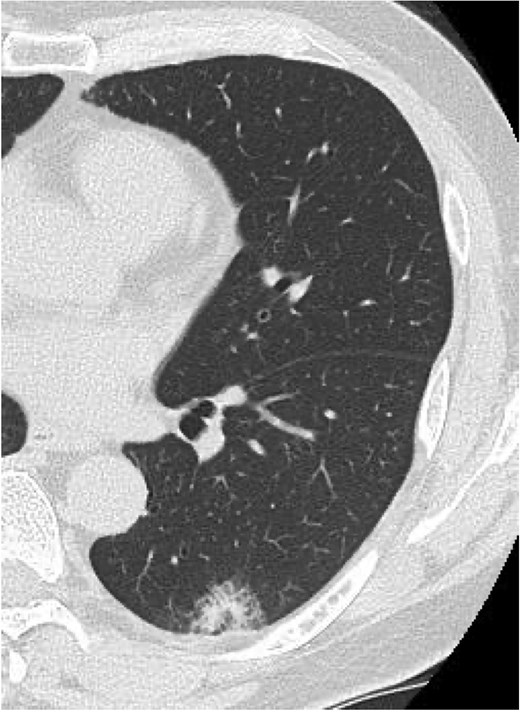

Serial chest imaging demonstrating pulmonary complications. (a) Postoperative day (POD) 10: Initial presentation without significant abnormalities. (b) POD 16: Peripheral ground-glass opacities (arrowheads). (c) POD 27: Patchy consolidation (solid arrows) with new ground-glass opacities and pleural effusion (open arrows). (d) POD 36: Progressive consolidation (solid arrows).

On POD 27, he was readmitted with fever (38.2°C) and respiratory failure. COVID-19 testing was negative. Chest computed tomography revealed patchy consolidations mixed with ground-glass opacities in the right upper lobe with notable expansion, and new ground-glass opacities in the right middle lobe and residual left upper lobe periphery (Fig. 2c). Findings excluded recurrent air leak or aspiration pneumonia. Despite antibiotic therapy, oxygen requirements increased to 2 L by POD 29.

Methylprednisolone pulse therapy (1 g/day for 3 days) was initially administered, followed by oral prednisolone (30 mg). However, oxygen requirements increased to 4 L on POD 31 (Fig. 3). On POD 36, a second methylprednisolone pulse course was initiated with cyclosporine A (150 mg) owing to progressive consolidation on chest imaging (Fig. 2d). Oxygen support was discontinued by POD 38, and he was discharged on POD 52. Follow-up image on POD 104 showed substantial radiological improvement (Fig. 4). Immunosuppressive medications were successfully tapered and discontinued by POD 329. This case was diagnosed as delayed-onset OP as a manifestation of post-acute COVID-19 syndrome, characterized by the biphasic clinical course and distinctive radiological progression occurring weeks after acute COVID-19 infection.